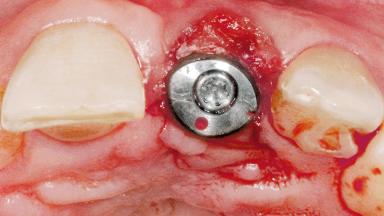

Late Flapless Placement of an Implant in a Maxillary Left Central Incisor Site

Type of Implants One-Piece

Attachment One-Piece

Bone Augmentation Horizontal|Staged